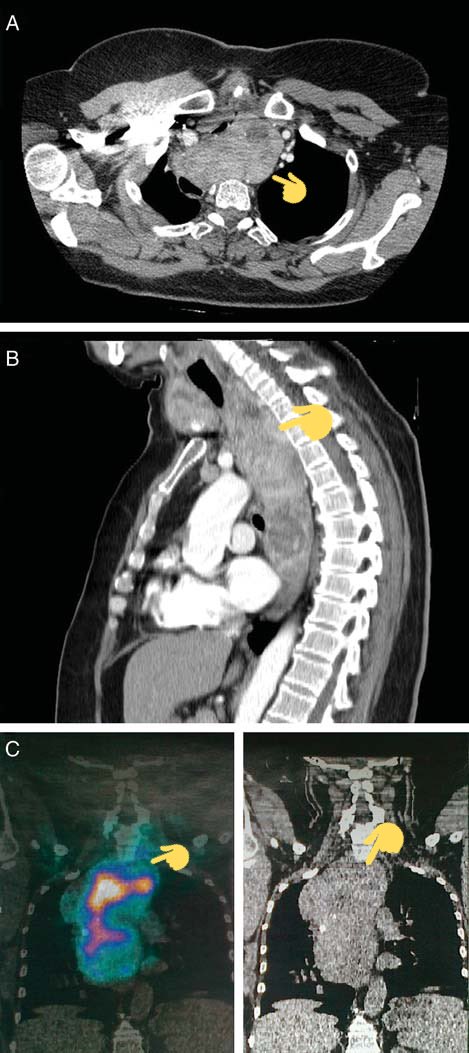

- طيب دكتوري طلب مني اشعة مقطعية للرقبة و الصدر ... ليش ؟

الجواب : اذا كانت متضخمة بشكل كبير و لها امتداد في الصدر .. يتم عمل الاشعة المقطعية حتى يتم كشف الامتداد ، اذا كانت لها اتصال مع الشرايين او الاوردة او القصبة الهوائية .

- امتداد الى الصدر